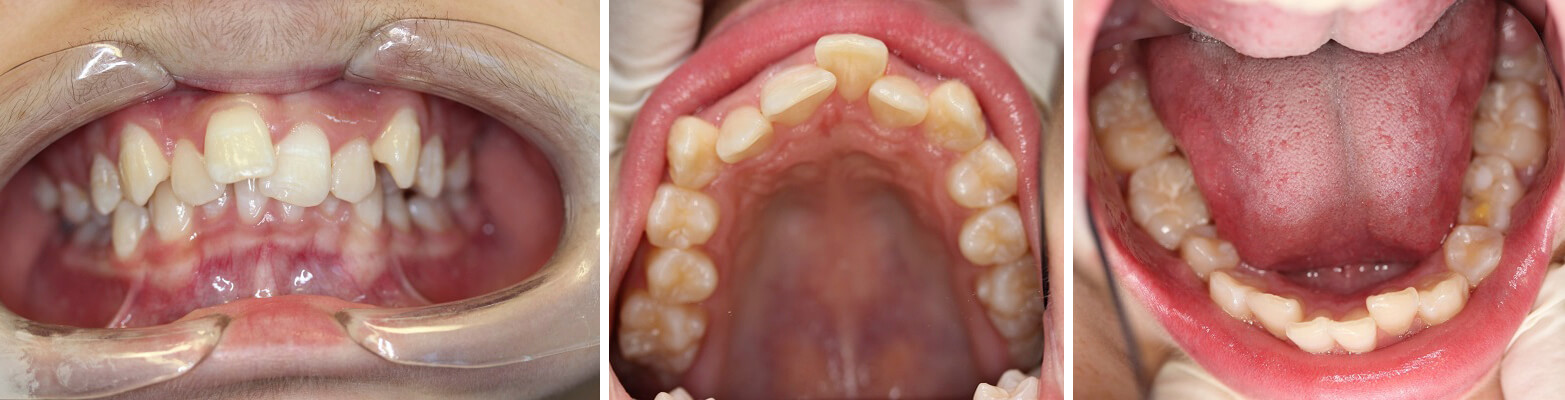

BEFORE

4 teeth were removed followed by orthodontic treatment with braces to achieve the perfect smile